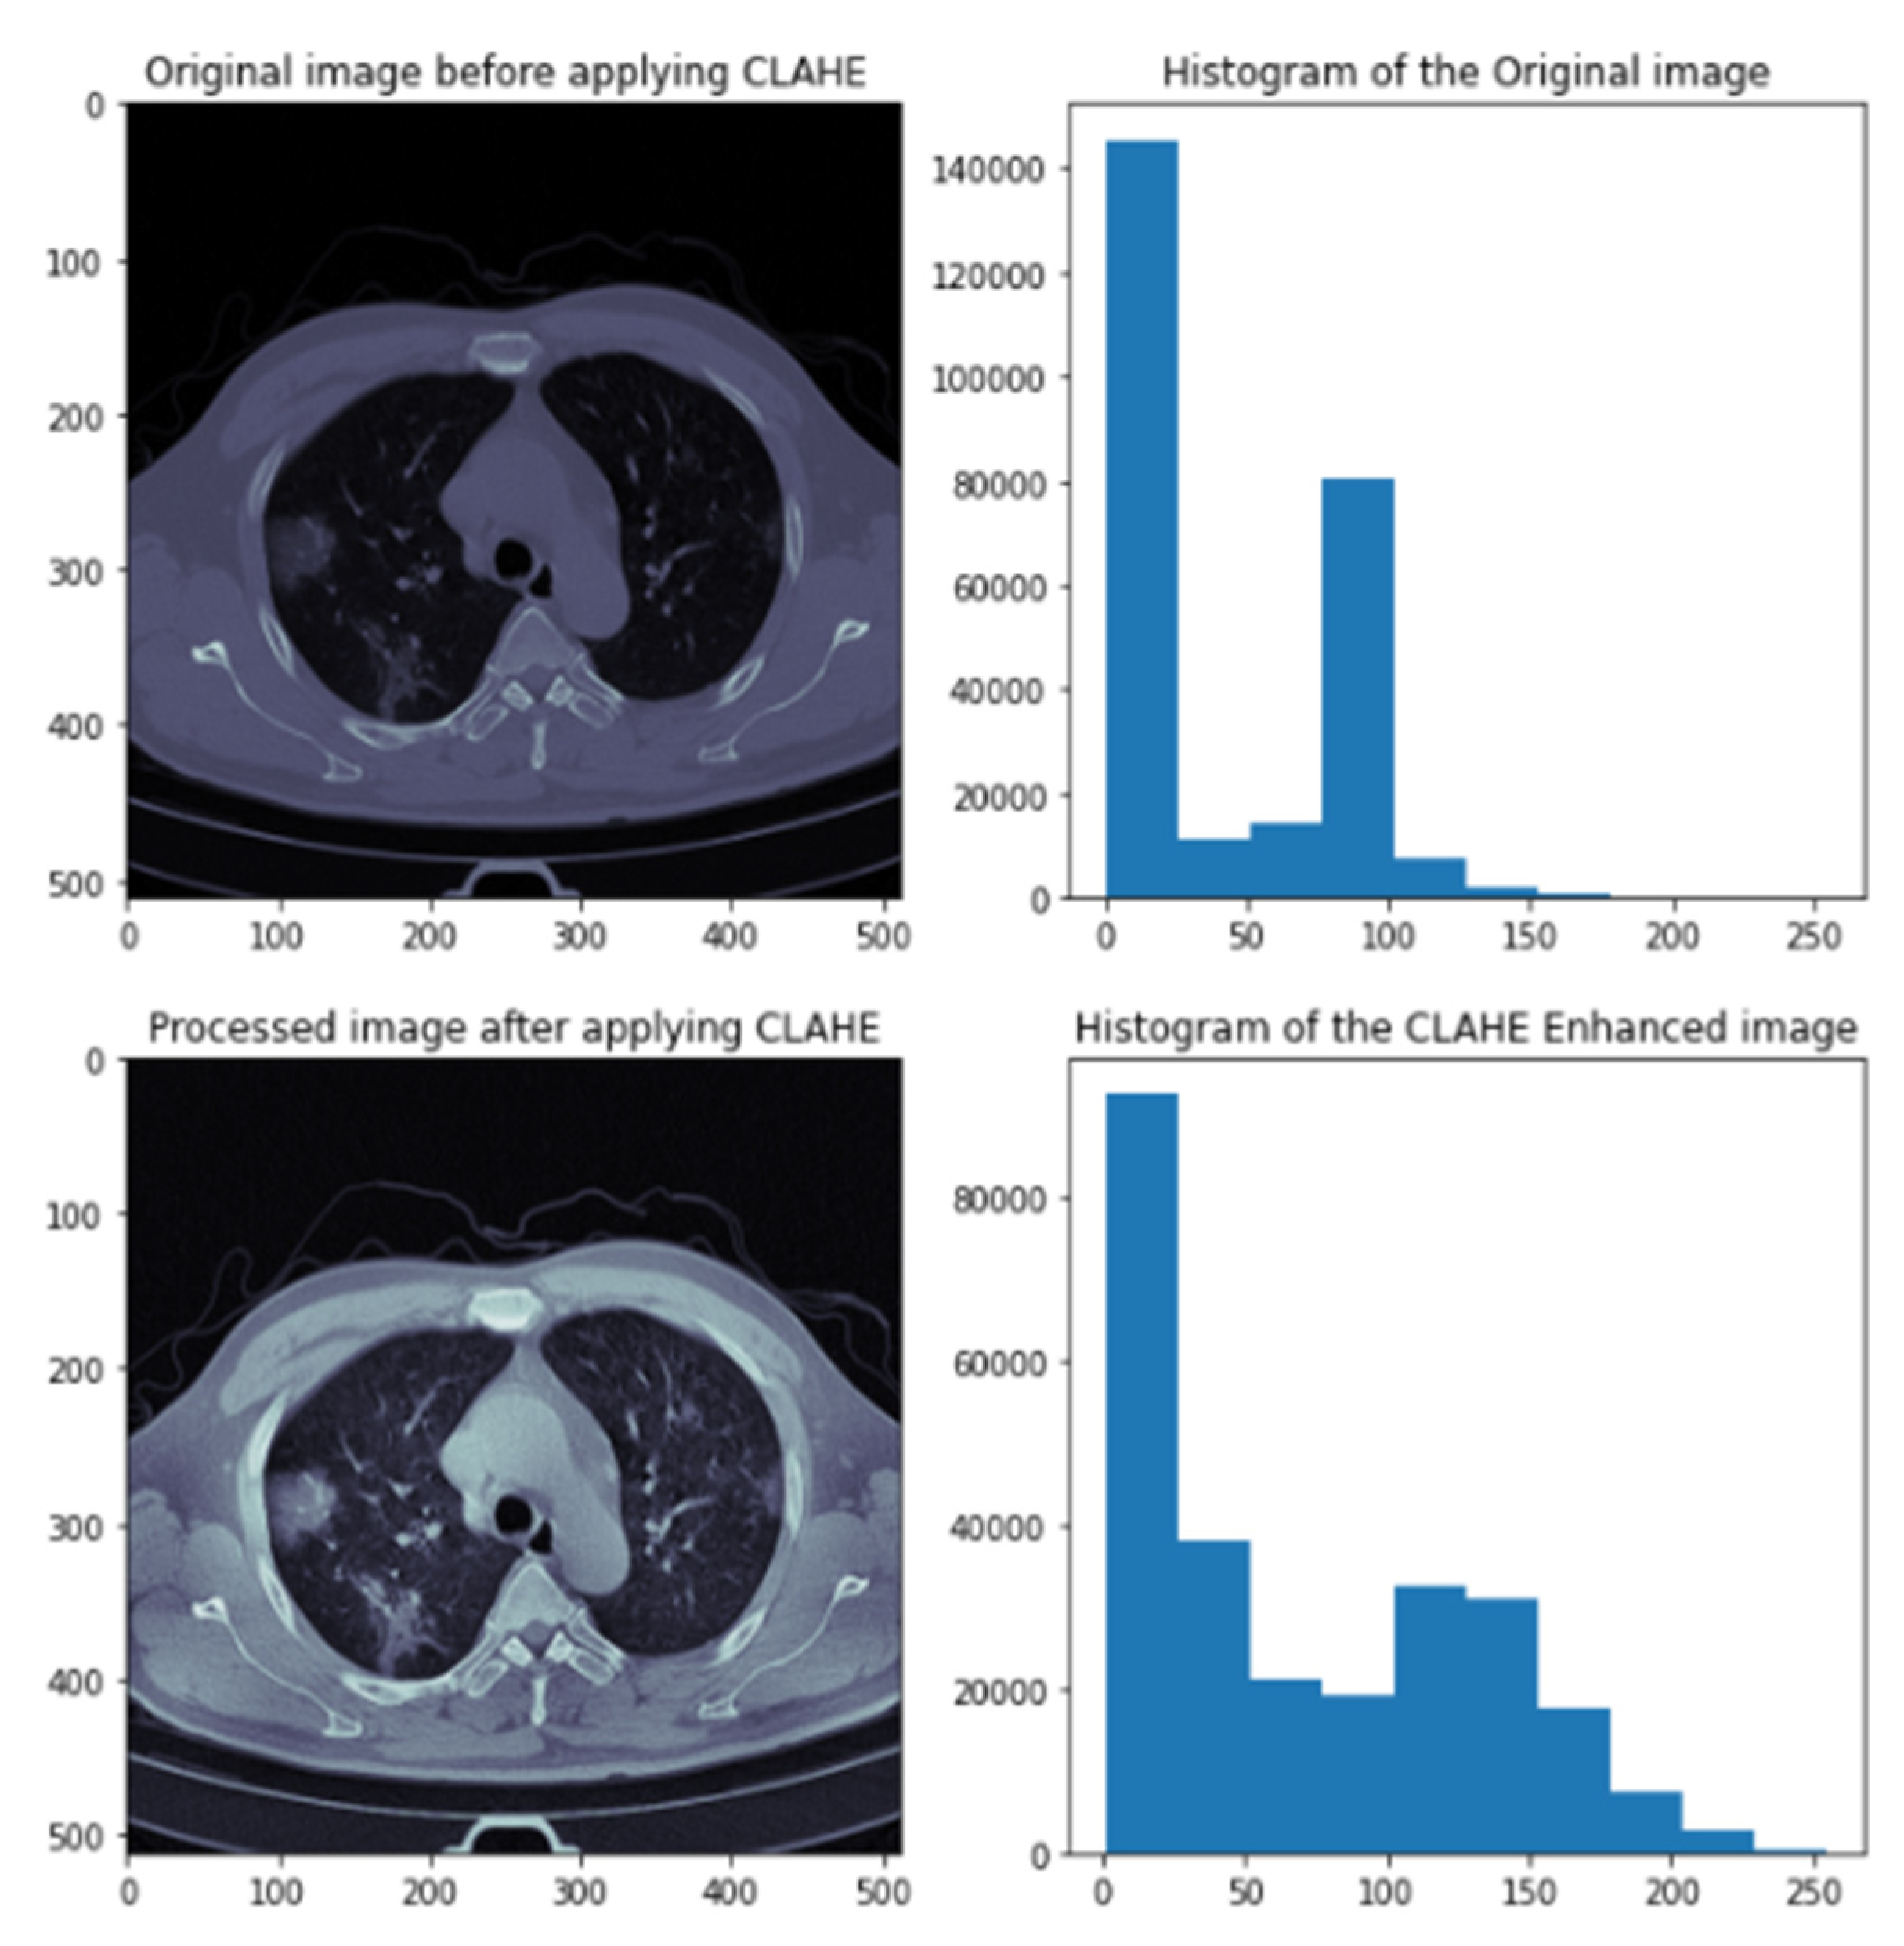

3.4. Data Preprocessing

- Pizer, S.M.; Amburn, E.P.; Austin, J.D.; Cromartie, R.; Geselowitz, A.; Greer, T.; ter Haar Romeny, B.; Zimmerman, J.B.; Zuiderveld, K. Adaptive histogram equalization and its variations. Comput. Vis. Graph. Image Process. 1987, 39, 355–368. [Google Scholar] [CrossRef]

- Zimmerman, J.; Pizer, S.; Staab, E.; Perry, J.; McCartney, W.; Brenton, B. An evaluation of the effectiveness of adaptive histogram equalization for contrast enhancement. IEEE Trans. Med. Imaging 1988, 7, 304–312. [Google Scholar] [CrossRef] [Green Version]

- Pizer, S.; Johnston, R.; Ericksen, J.; Yankaskas, B.; Muller, K. Contrast-limited adaptive histogram equalization: Speed and effectiveness. In Proceedings of the First Conference on Visualization in Biomedical Computing, Atlanta, GA, USA, 22–25 May 1990; pp. 337–345. [Google Scholar] [CrossRef]